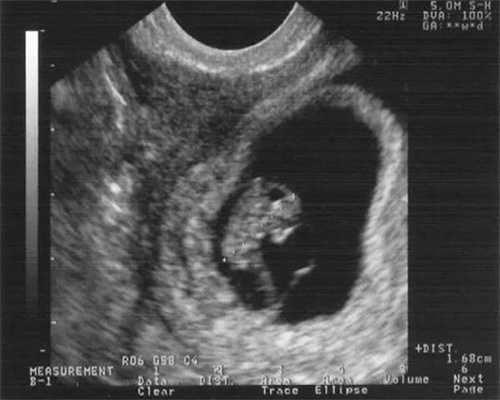

医生不断鼓励王女士,让她不要过于紧张和焦虑,并调整了她的排卵方案,这次排卵移植14天后,王女士终于成功怀孕了,验血hcg出现了明显的翻倍。